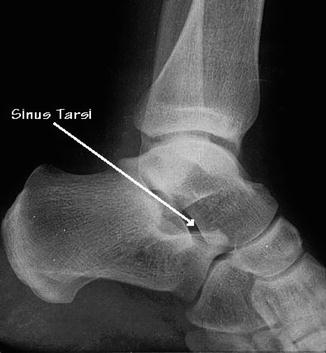

The tarsal sinus contains blood vessels nerves fat and a ligamentous complex which is comprised of 3 4. What is sinus tarsi syndrome pain localized at the eye of the foot often the result of an ankle sprain foot inversion or foot eversion. On the articulated foot th calcaneal sulcus on calcaneus and the sulcusl tali on the talus form a canal sinus tarsi for the lodgement of the interosseous talocalcaneal ligament.

The sinus tarsi represents an anatomical space in the foot that is surrounded with the talus and calcaneus bones the talonavicular and posterior subtalar joint. Medial talocalcaneal interosseous ligament ligament of the sinus tarsi. The sinus tarsi is a tunnel between the talus and the calcaneus that contains strucures that contribute to the stability of the ankle and to its proprioception but can get damaged in the sinus tarsi.

The sinus tarsi consists of fatty tissue arterial vessels joint recesses at the posterior side nerve fibers and five ligaments. The sinus tarsi is a space filled by the extensor digitorum brevis muscle and its fat pad that lies between the lateral aspects of the talus and calcaneus. The most common sinus tarsi symptoms are.